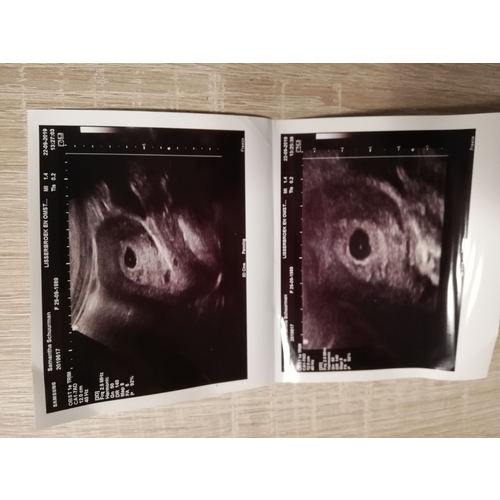

Ik heb het ook gehad op 5weken en 4dagen. Naar gynceloog geweest en idd ze zagen 2 mooie vruchtzakjes zitten. Maar ken je gevoel! Ik dacht dat over was!

Maar idd innestelingsbloed ..